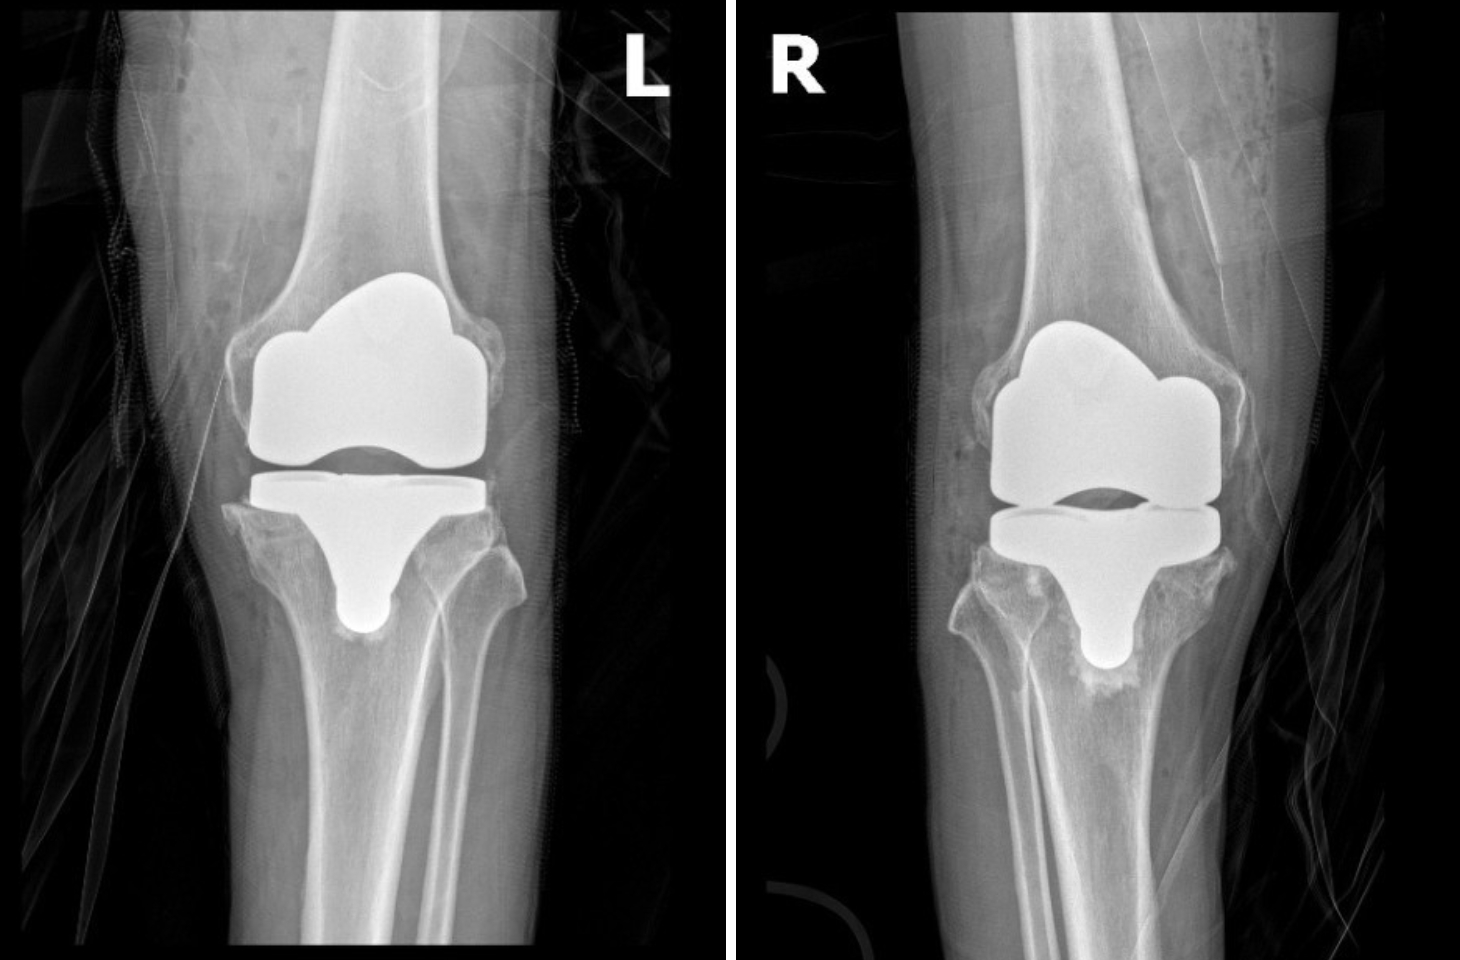

Phim chụp khớp gối bệnh nhân Thau sau phẫu thuật khớp nhân tạo vừa vặn với trục chân, vận động trơn tru

Trong gần 2 tiếng phẫu thuật, ông Thau không cần phải truyền máu và chỉ số huyết áp luôn trong trạng thái ổn định. Chỉ 1 ngày sau phẫu thuật, ông đã tỉnh táo và bắt đầu chế độ tập Phục hồi chức năng sớm, từng bước khôi phục vận động.“Tôi vui lắm, lâu lắm rồi tôi mới có cảm giác không đau chân và ngủ ngon như vậy. Cứ cái đà này thì chắc chỉ mấy tháng nữa là tôi đi bộ thể dục được cùng mấy ông bạn rồi!” - Bệnh nhân Thau mừng rỡ nói.